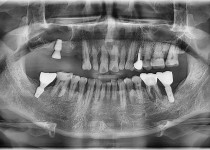

만 52세 전악 상악, 하악 전체 임플란트…

만 56세 상 하악 임플란트 증례